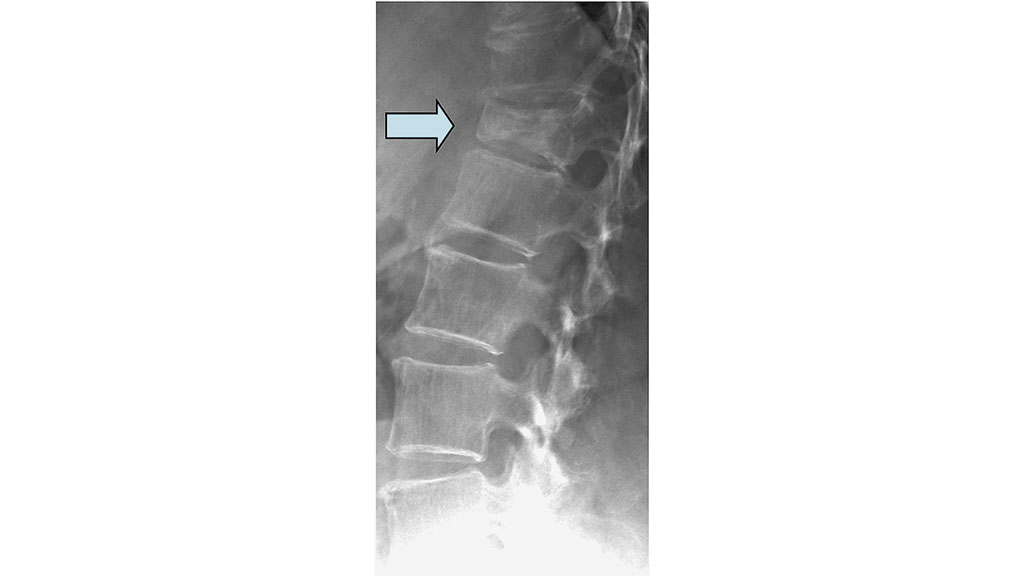

Bildgebende Standarddiagnostik ist die nativradiologische Darstellung des betroffenen Wirbelsäulenabschnittes in zwei Ebenen. Bei diagnostizierter Fraktur (Abb. 1) sollte bei Verdacht auf eine alte Wirbelkörperfraktur zusätzlich nativradiologisch eine Hypomochlionaufnahme (Abb. 2) im Liegen angefertigt werden, um erste Hinweise auf eine mögliche Wirbelkörperpseudarthrose zeitnah zu erhalten. Weiterführend wird mittels Magnetresonanztomografie (MRT) geklärt, ob es sich um eine frische Fraktur handelt (Steigerung der Intensität in den STIR- oder TIRM-Sequenzen) (Abb. 3) und ob möglicherweise ligamentäre Strukturen verletzt sind, um eine mögliche B- oder C‑Verletzung (nach AO: Arbeitsgemeinschaft Osteosynthese) der Wirbelsäule nicht zu übersehen. Gegebenenfalls wird die Diagnostik mittels Computertomografie (CT) vervollständigt, um die Frakturform exakt evaluieren und klassifizieren zu können. Echte Operationsindikationen sind Berstungsfrakturen der Wirbelkörper sowie B- und C‑Verletzungen der Wirbelsäule 22.